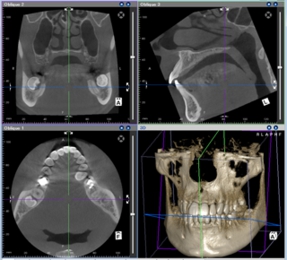

1. デジタルX線撮影装置、CT撮影装置

デジタルレントゲンの長所は、被曝量を減らすことときれいな画像(=正確な診断)の両方が得られることです。またCT撮影装置は三次元的な位置の把握が非常に簡単にでき、従来の二次元画像ではとても見えなかったことが容易にわかることで、これらにより診断精度が格段に上がります。